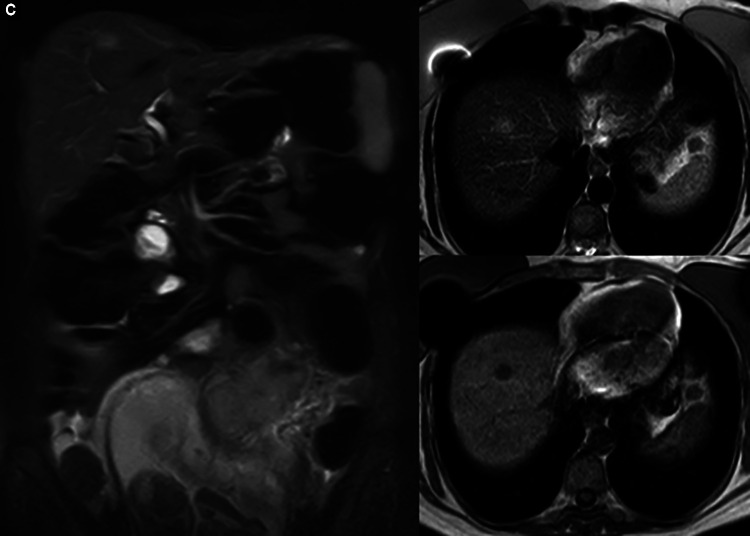

Case description: A 45-year-old female primigravid, pregnant woman, in the 20th week of gestation presented with complaints of multiple episodes of bloody diarrhea and tenesmus for the past 3 weeks. This was accompanied by poor appetite and weight loss (15 kg) since the onset of pregnancy. The patient also complained of lower back and abdominal pain. Investigations confirmed an obstructing rectosigmoid mass (15 cm) that could not be passed. The patient's pregnancy was terminated, and chemotherapeutic treatment was initiated.